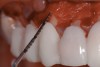

Fig 3. Initial parasulcular scalloped incisions.

Figure 3

Following anesthesia, a scalloped incision was made on the keratinized tissue (Figure 3). In the interproximal area, a papilla-sparing incision was made. A full-thickness flap was raised to give access to the underlying bone (Figure 4). Both osteoplasty and ostectomy were performed to position the bone crest approximately 2 mm to 3 mm from the CEJ (Figure 5). The gingival tissue was repositioned, coinciding with the initial labial incision and the interproximal papilla. Interrupted sutures were placed (Figure 6), which were removed 7 days following the surgery.